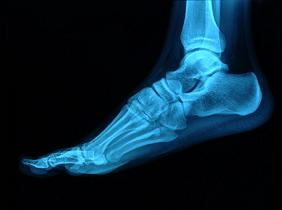

La talalgia es el nombre que se le da al dolor en el talón. Este tipo de patología es muy frecuente, sobre todo en deportistas...